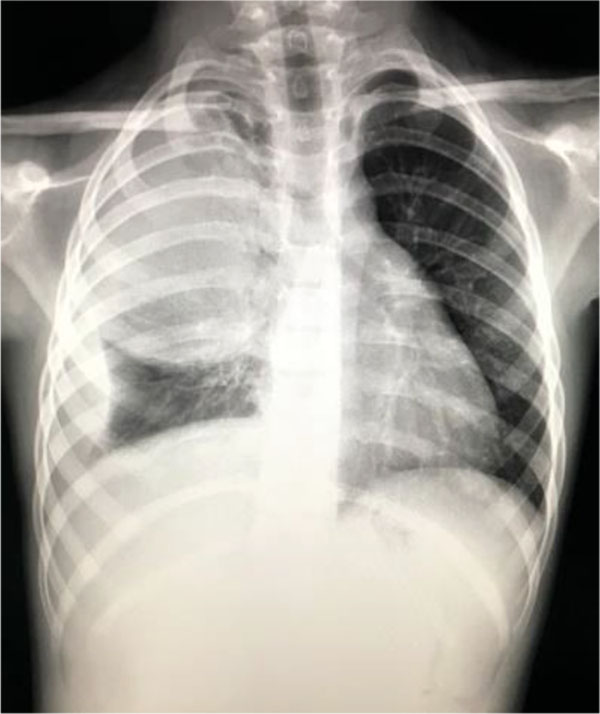

The medical history of the patient revealed that she has been diagnosed with acute myeloid leukemia (positive FLT3-ITD mutation – associated with unfavorable prognosis), in remission for 1,5 years. At admission she presented influenced general status, pale skin, clinical aspect of ulcer-necrotic tonsillitis, fever, irritative cough, vesicular breath sounds, without abnormal breath sounds. Blood tests revealed an increased number of leukocytes (34870/mmc) with predominance of neutrophils (80%) and an important inflammatory syndrome (CRP=126mg/l). Bone marrow aspirate revealed late medullary relapse (42% blasts). In that case we’ve started broad spectrum antibiotics (Meropenem, Ciprofloxacin and Metronidazole) that determined the relieving of acute symptoms. After that, chemotherapy was started with low dose cytarabine. In the 11th day of hospitalization, the patient developed high fever, shortness of breath, productive cough and severe post chemotherapy neutropenia (20/mmc). Chest x-ray was consistent for bronchopneumonia. (Fig.11) Therefore, she received treatment with Linezolid and Teicoplanin for the next 10 days. Despite this therapy, the girl had no clinical improvement and maintained respiratory symptoms. For the next 5 days she received Linezolid, Teicoplanin and Fluconazole with poor clinical and radiologic evolution. For the next 7 days we’ve changed Fluconazole with Voriconazole. This treatment having a major impact on both clinical and radiological evolution - regression of codensation and the disapearance of the other 2 opacities.

Fig. 11 Medium intensity opacity, inhomogenous, located at the base of right lung and 2 other opacities located retrocardiac

Fig.12 Slow favorable evolution: regression of codensation and the disapearance of the other opacities